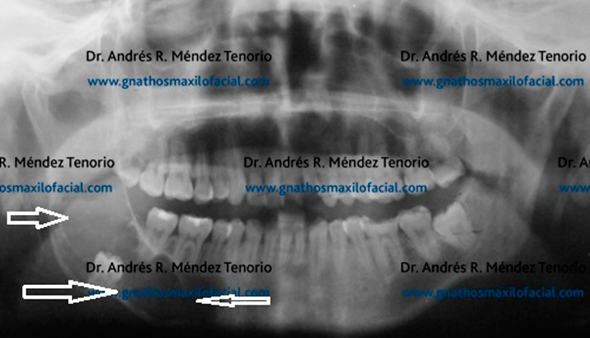

|

| Radiografia panorámica mostrando 3os molares. Del lado izquierdo (flecha) ante la ausencia del inferior, el 3er molar superior se ha salido de su plano y lastima la mucosa de la mandíbula |